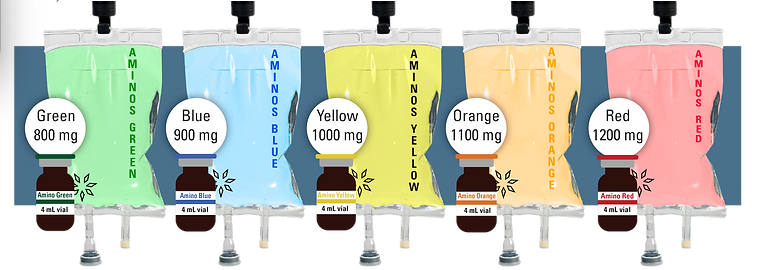

A typical NAD IV treatment session usually lasts between 4 and 8 hours. However, the exact duration can vary depending on the dosage, the specific protocol being followed, and the individual’s response to the treatment.

Because these formulas are composed of very simple amino acids – the natural building blocks of protein and nicotinamide adenine dinucleotide (NAD) a natural enzyme cofactor, they are inherently very safe. Your doctor will monitor you during the entire treatment to prevent unwanted reactions.